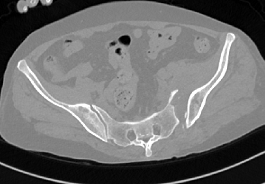

术前CT和术后CT比较

近日,市四医院骨一科收治了一位特殊患者,该患者因车祸伤致骨盆多处骨折,经CT检查后,发现该患者骨盆有大大小小的骨折达8-10处,左侧骶髂关节明显脱位,双侧耻骨骨折。

整个手术1小时内完成,通过术后CT影像证实3D打印导航模板引导骶髂螺钉置入安全、准确、创伤较小,手术时间短,患者也很快得到了较好的恢复。